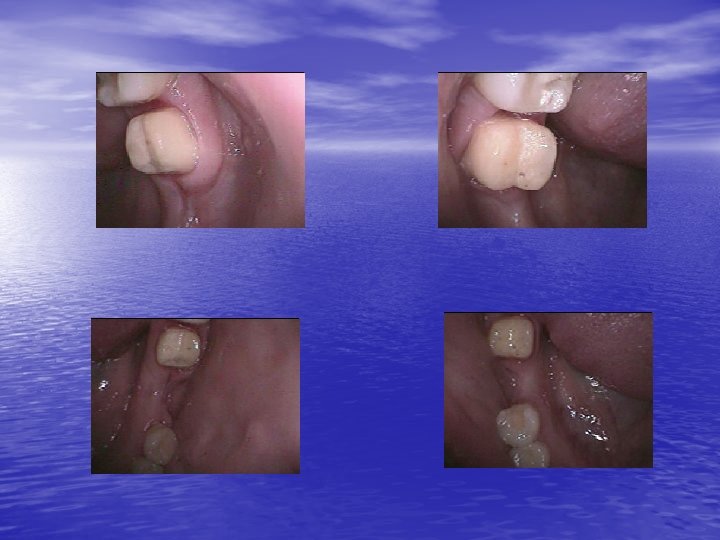

Third clinical case